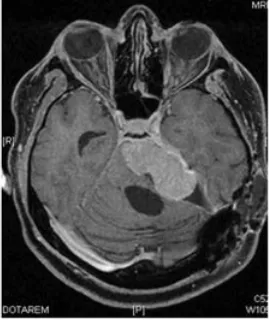

然而恶化的速度远超预期。根治性切除手术后不过三个月,肿瘤即以极强的侵袭性迅速复发,并对脑干造成严重压迫。为维系基本生命功能,患者紧急接受了第二次手术以实施脑干减压。这一次的病理结果表明,肿瘤已进一步去分化,转化为间变性软组织肉瘤,神经源性标记物S100蛋白的表达已完全丧失。

最终结局与临床警示

在计划启动辅助放疗的等待期内,肿瘤在短短四周之内再度复发。疾病的恶性程度与增殖速度,已超出现有所有治疗手段所能干预的时间窗口。末次手术后一个月,残余肿瘤再次侵袭性生长,对脑干造成致命性压迫,患者最终离世。